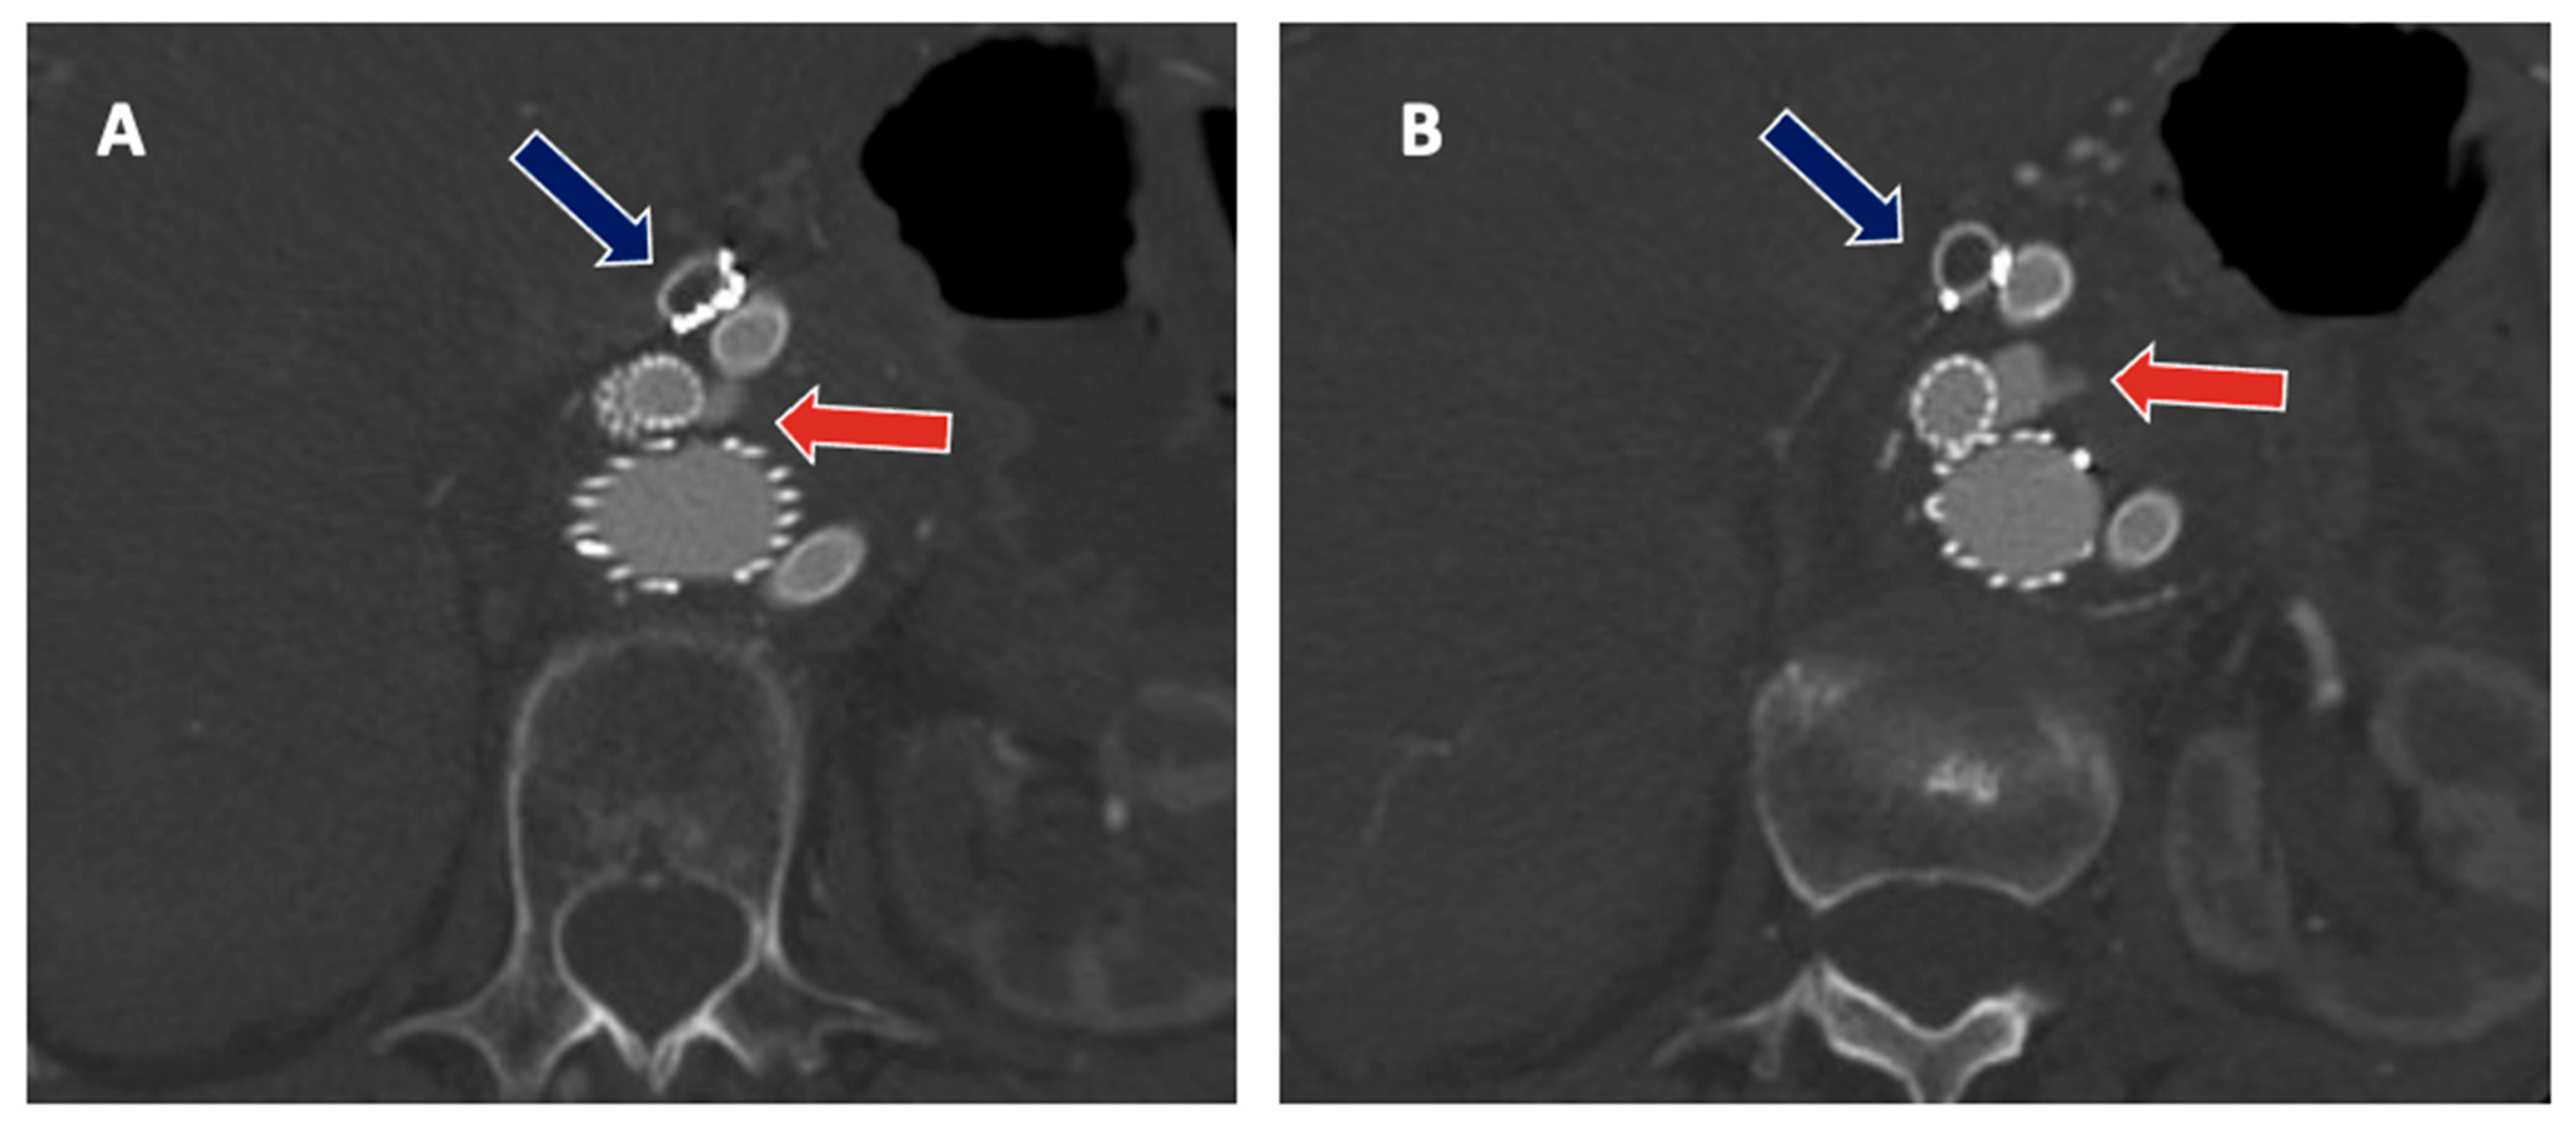

Indeed, the most frequent treatment-related complications that may arise following F/BEVAR interventions are represented by TV-related endoleaks (EL), which may occur in 1 out of 10 patients on CTA at discharge (Figure 3), although different adverse events may arise that can significantly impact patients’ health and quality of life [25,26]. TV instability was defined by a composite of any stent stenosis, separation, or type IC or type IIIC EL requiring reintervention and stent occlusion, aneurysm rupture or death due to TV-related complications [26]. Although it may seem likely that less complex FEVAR procedures will entail lower risks to the patients as compared with more extensive BEVAR interventions, the current evidence is mixed, as experienced operators may achieve comparable outcomes. Nonetheless, the length of aortic coverage and number of TV involved will likely remain as the main contributors of peri-operative adverse events also at centers of excellence and should, therefore, be included in the decision-making process [27]. Certainly, the team and surgeons’ experience are fundamental to preventing and recognizing early postoperative complications to ensure prompt and effective treatment. Furthermore, the rate of mortality and major complications after complex aortic surgery appears to be related to the surgical volume of the center, as shown by prior studies, mainly relating to the outcomes from major centers [28]. More than 154,000 patients underwent OSR and EVAR for intact AAA were analyzed by Scali and colleagues to identify an optimal center volume associated with the most significant mortality reduction after OSR; 65,745 underwent OSR and a significant inverse relationship between increasing center volume and lower peri-operative mortality after intact and ruptured OAR was evident (p < 0.001). An annual center volume of between 13 and 16 procedures per year (PY) was associated with the most significant mortality reduction after intact OAR (adjusted predicted mortality <13 PY 4.6% vs. 3.1% for centers with ≥13 PY) [29]. Data from a recent nationwide mandatory quality registry showed similar results for 694 patients, treated by FEVAR (539) and BEVAR (155). The perioperative mortality of complex EVAR was 9.1% in hospitals with a volume of <9 PY and 2.5% in hospitals with a volume of ≥13 PY (p = 0.008). The annual volume of ≥13 PY was associated with less perioperative mortality compared to hospitals with a volume of <9 PY [28]. Whether these outcomes can be extrapolated to low-volume operators to achieve similar outcomes is unclear. However, there is evidence that suggests a learning curve effect may exist for F/BEVAR interventions. Together with improved patient selection, these factors may substantially contribute to enhanced surgical outcomes [30]. Lately, the concept of failure to rescue (which is a composite endpoint defined as peri-operative death after experiencing at least one major complication) has emerged as an additional and more sensitive marker for team quality assessment in aortic interventions. Future research may also be directed toward better understanding of failure to rescue after complex endovascular aortic repair, as this remains relatively unaddressed in the available literature [31].

Figure 3.

(A,B) Type IIIb endoleak from the right renal stent (red arrow), with sac enlargement and simultaneous asymptomatic thrombosis of the celiac trunk stent-graft (blue arrow).